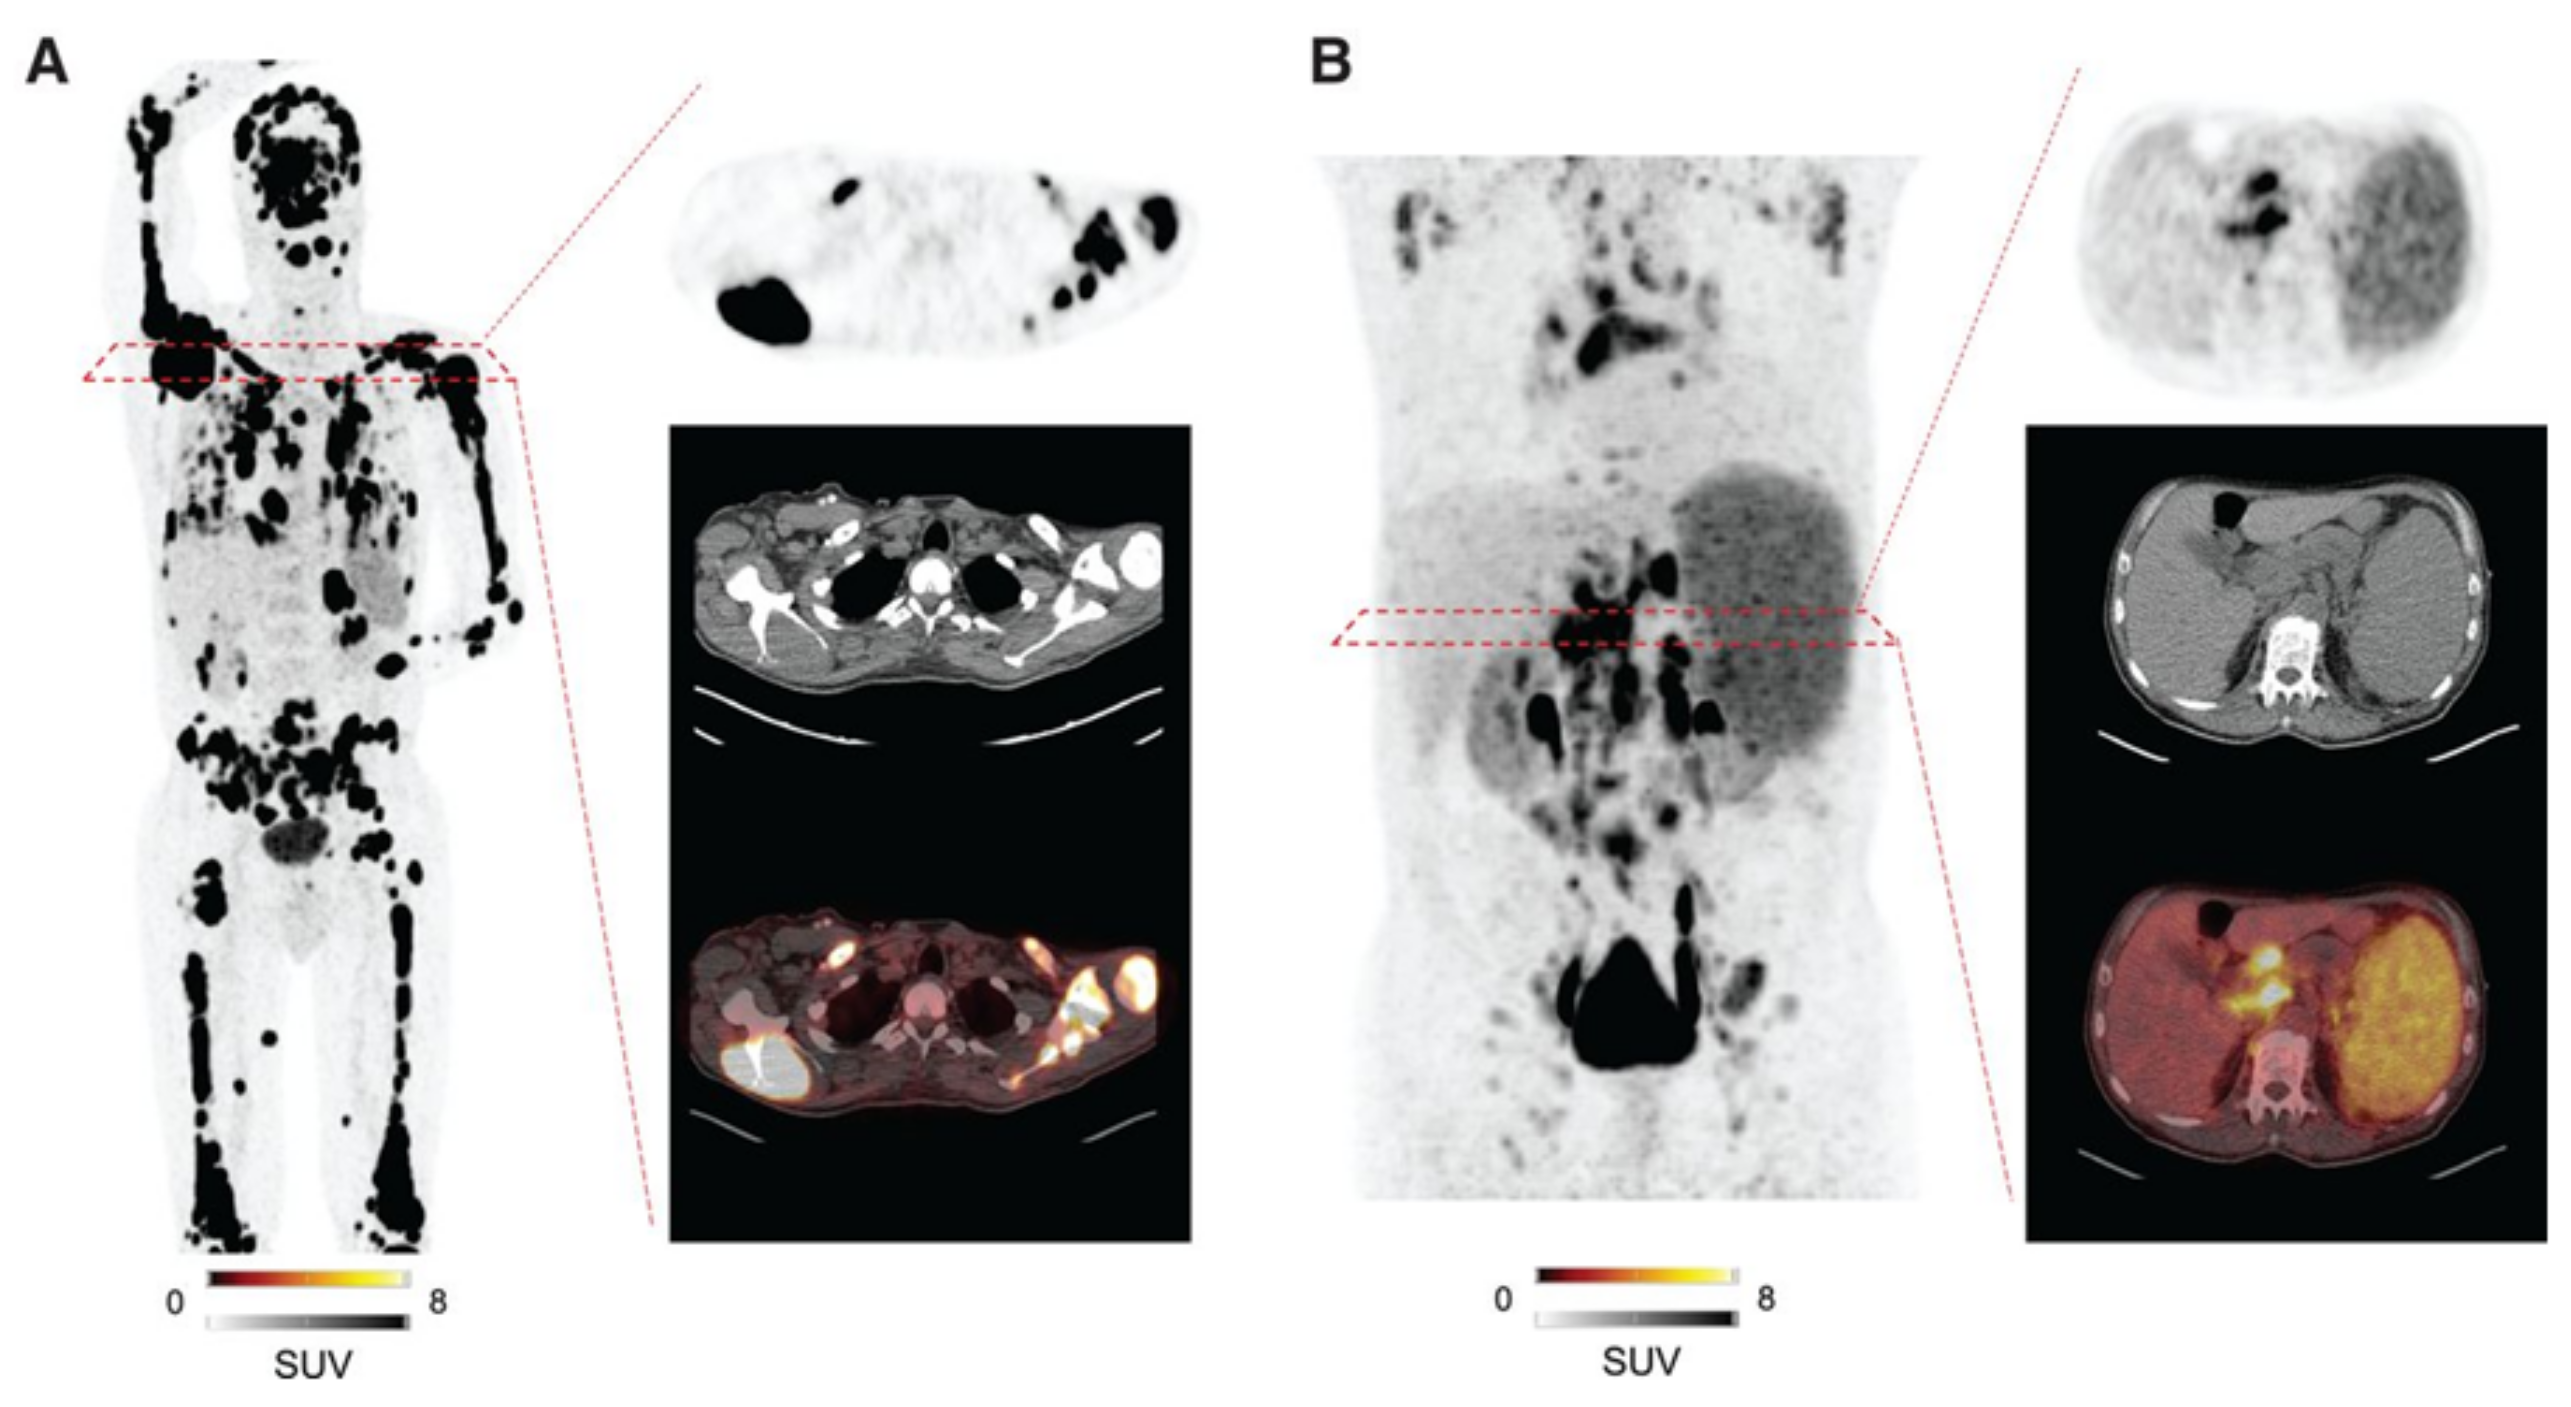

- Chen, X.; Wang, S.; Lai, Y.; Wang, G.; Wei, M.; Jin, X.; Ding, J.; Zhang, Y.; Shi, Y.; Wang, F.; et al. Fibroblast Activation Protein and Glycolysis in Lymphoma Diagnosis: Comparison of 68Ga-FAPI PET/CT and 18F-FDG PET/CT. J. Nucl. Med. 2023, 64, 1399–1405. [Google Scholar] [CrossRef]